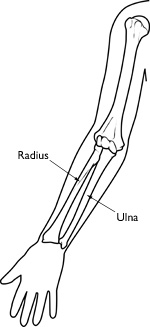

Your forearm is made up of two bones, the radius and ulna. In most cases of adult forearm fractures, both bones are broken.

AnatomyIf you hold your arms at your side with your palms facing up, the ulna is the bone closest to your body and the radius is closest to your thumb. The ulna is larger at the elbow — it forms the "point" of your elbow — and the radius is larger at the wrist.

The bones of your forearm are the radius and the ulna.